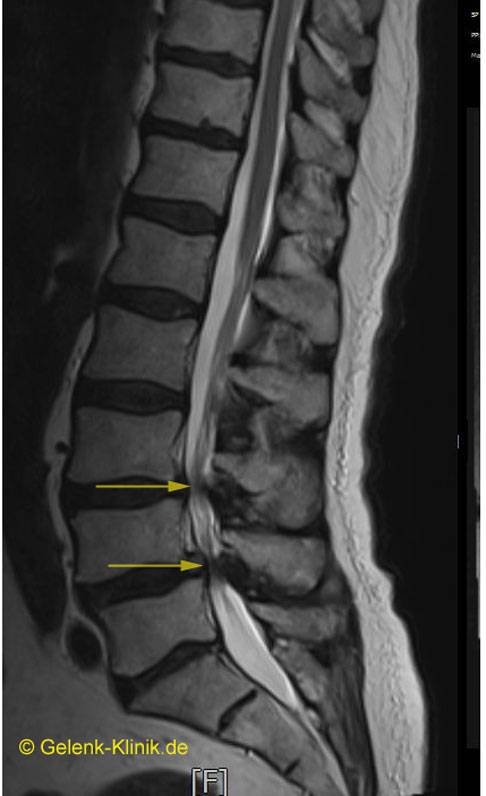

Zusätzlich zur klinischen und neurologischen Untersuchung zieht der Rückenspezialist bildgebende Verfahren heran. Unerlässlich zum Nachweis einer Wirbelkanalstenose ist – neben der obligatorischen Röntgenuntersuchung – eine Magnetresonanztomografie (MRT).

Die MRT zeigt z. B. die einengenden Spondylophyten oder die Vorwölbung einer höhenverminderten, dehydrierten Bandscheibe in den Spinalkanal hinein. Manchmal sind auch mehrere Stenosen sichtbar. Nur durch genaue Abstimmung der radiologischen Befunde mit den Ergebnissen der neurologischen Untersuchung und der Beschwerden des Patienten lässt sich die klinische Relevanz der sichtbaren Engstellen deuten.